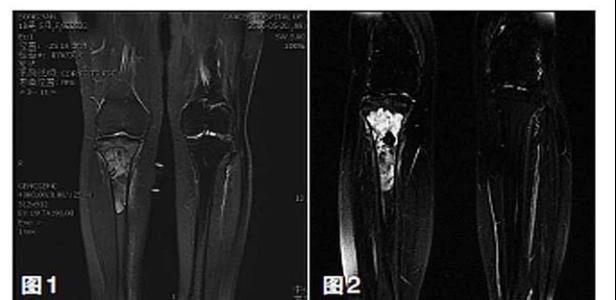

新輔助化療的目的是盡早殺滅遠(yuǎn)處微小轉(zhuǎn)移灶,縮小腫瘤及周圍炎性水腫反應(yīng)區(qū),以利于后續(xù)的保肢手術(shù);觀察腫瘤對化療的敏感性,為進(jìn)一步指定個體化的術(shù)后化療方案奠定基礎(chǔ)。骨肉瘤新輔助化療下的保肢治療如下圖所示: